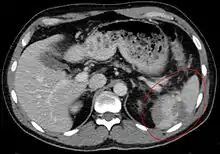

| Spleen ruptured by trauma | |

Splenic rupture is usually evaluated by FAST ultrasound of the abdomen.[3] Generally this is not specific to splenic injury; however, it is useful to determine the presence of free floating blood in the peritoneum.[3] A diagnostic peritoneal lavage, while not ideal, may be used to evaluate the presence of internal bleeding a person who is hemodynamically unstable.[4] The FAST exam typically serves to evaluate the need to perform a CT.[4] Computed tomography with IV contrast is the preferred imaging study as it can provide high quality images of the full peritoneal cavity.[3]